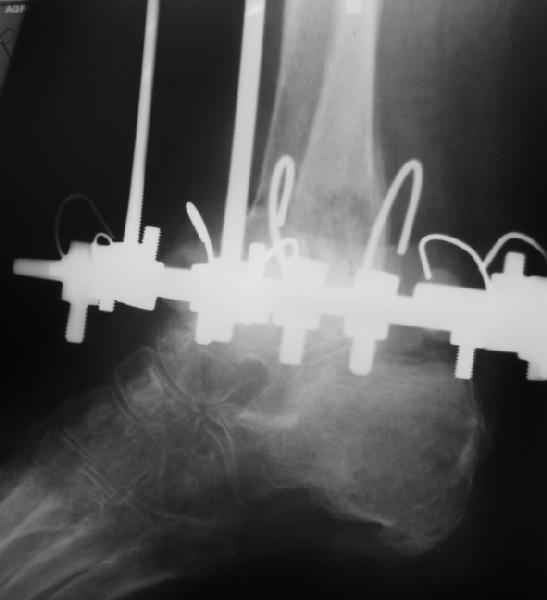

Пациентка 56лет поступила через 5,5 мес. после открытого 2-х лодыжечного перелома, наружного вывиха правой стопы, осложнённого гнойным артритом.

через 3 недели после травмы в ОКБ выполнена артротомия, некрсеквестрэктомия б/берцовой кости, ещё через неделю - аутодермопластика по Тиршу. К нам больная поступила через 5,5 мес. Выполнен ЧКО, остеотомия м/берцовой кости, аппаратное вправление вывиха. Планируется артродез голеностопного сустава. По медиальной поверхности голени на месте аутодермопластики сформировался грубый рубец, спаянный с б/берцовой костью. Больная ходит на костылях с частичной опорой на правую стопу. ВОПРОС: 1) возможно ли в данной ситуации обойтись компрессионным артродезом в АВФ?2) какой вид кожной пластики и в какие сроки целесообразен?

Возможно, но тогда дополнить аппарат модулями на стопе. На фото стопа в эквинусе. Сомнительно, что фиксация только за таран удержит всю стопу, тем более при разрешенной нагрузке.

"На фото стопа в эквинусе."

Обратите внимание на установку тарана на рентгене!

"Сомнительно, что фиксация только за таран удержит всю стопу, тем более при разрешенной нагрузке."

ЗАЧЕМ фиксировать всю стопу? Наоборот, необходимо создать гипер подвижность в суставах Лисфранка, Шопара и подтаранном для нормального функционирования конечности после формирования анкилоза в голеностопном суставе.

Другими словами, вы предлагаете закрытый внесуставной артродез аппаратом внешней фиксации без резекции суставных концов. Предположу, что рассчитываете на анкилозирование через разрушение/некроз гиалинового хряща сустава. По крайней мере смело, с анамнезом гнойного артрита.

2."Обратите внимание на установку тарана на рентгене! "

В самом деле, снимки некачественные - таран в ротации. Но даже по ним видно, что установка стопы минимум 104 градуса. С одной стороны - В Илизаровской технике пишут, что для женщин допустимо и 110. С другой - почему-то в цивилизованном мире настаивают на четких 90.

А если еще лучше присмотреться, таран в переднем подвывихе, что не кажется допустимым.